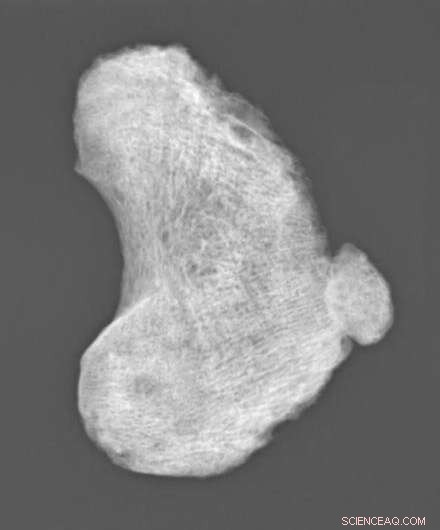

A picture of the child's knee cap X-Ray. Credit: S. Inskip, Leicester University.